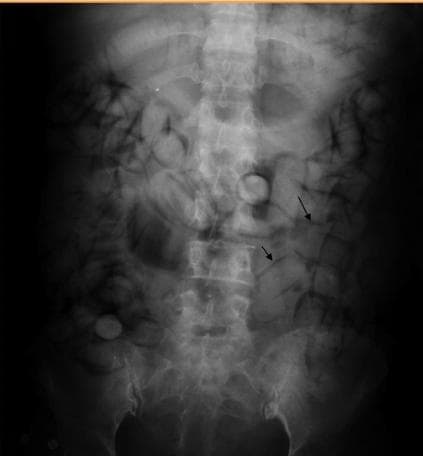

1. Plain Radiography (X-ray)

Plain radiography, or X-ray imaging, is the first-line diagnostic tool to detect foreign bodies within the gastrointestinal tract. It is widely available, cost-effective, and relatively quick, making it the most common imaging modality in suspected body packing or stuffing cases.

Key Features: Drug packets appear as oval, well-defined radiopaque densities in the stomach or intestines.

Advantages: Rapid assessment, widely available, and non-invasive.

Limitations: X-ray sensitivity depends on the type of drug packaging. Some packets, especially those wrapped in non-radiopaque materials, may be difficult to detect. While X-ray remains a commonly used imaging modality for suspected body packers, recent studies indicate that CT scans are significantly more sensitive in detecting illicit drug packets and identifying complications such as rupture or obstruction. A five-year retrospective analysis found that 94.4% of drug packets were detected on CT scans, compared to significantly lower detection rates on X-rays (Gheshlaghi et al., 2021).